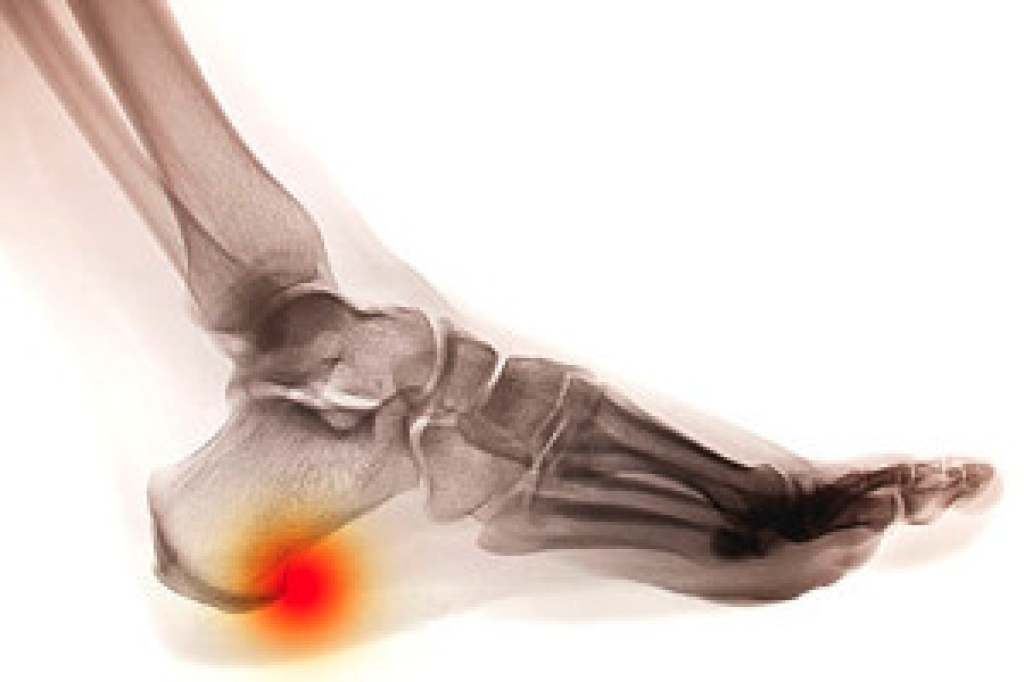

Cuboid syndrome is a common cause of lateral foot pain, which is pain on the outside of the foot. The condition may happen suddenly due to an ankle sprain, or it may develop slowly overtime from repetitive tension through the bone and surrounding structures.

A common symptom of cuboid syndrome is pain along the outside of the foot which can be felt in the ankle and toes. This pain may create walking difficulties and may cause those with the condition to walk with a limp.

Diagnosis of cuboid syndrome is often difficult, and it is often misdiagnosed. X-rays, MRIs and CT scans often fail to properly show the cuboid subluxation. Although there isn’t a specific test used to diagnose cuboid syndrome, your podiatrist will usually check if pain is felt while pressing firmly on the cuboid bone of your foot.